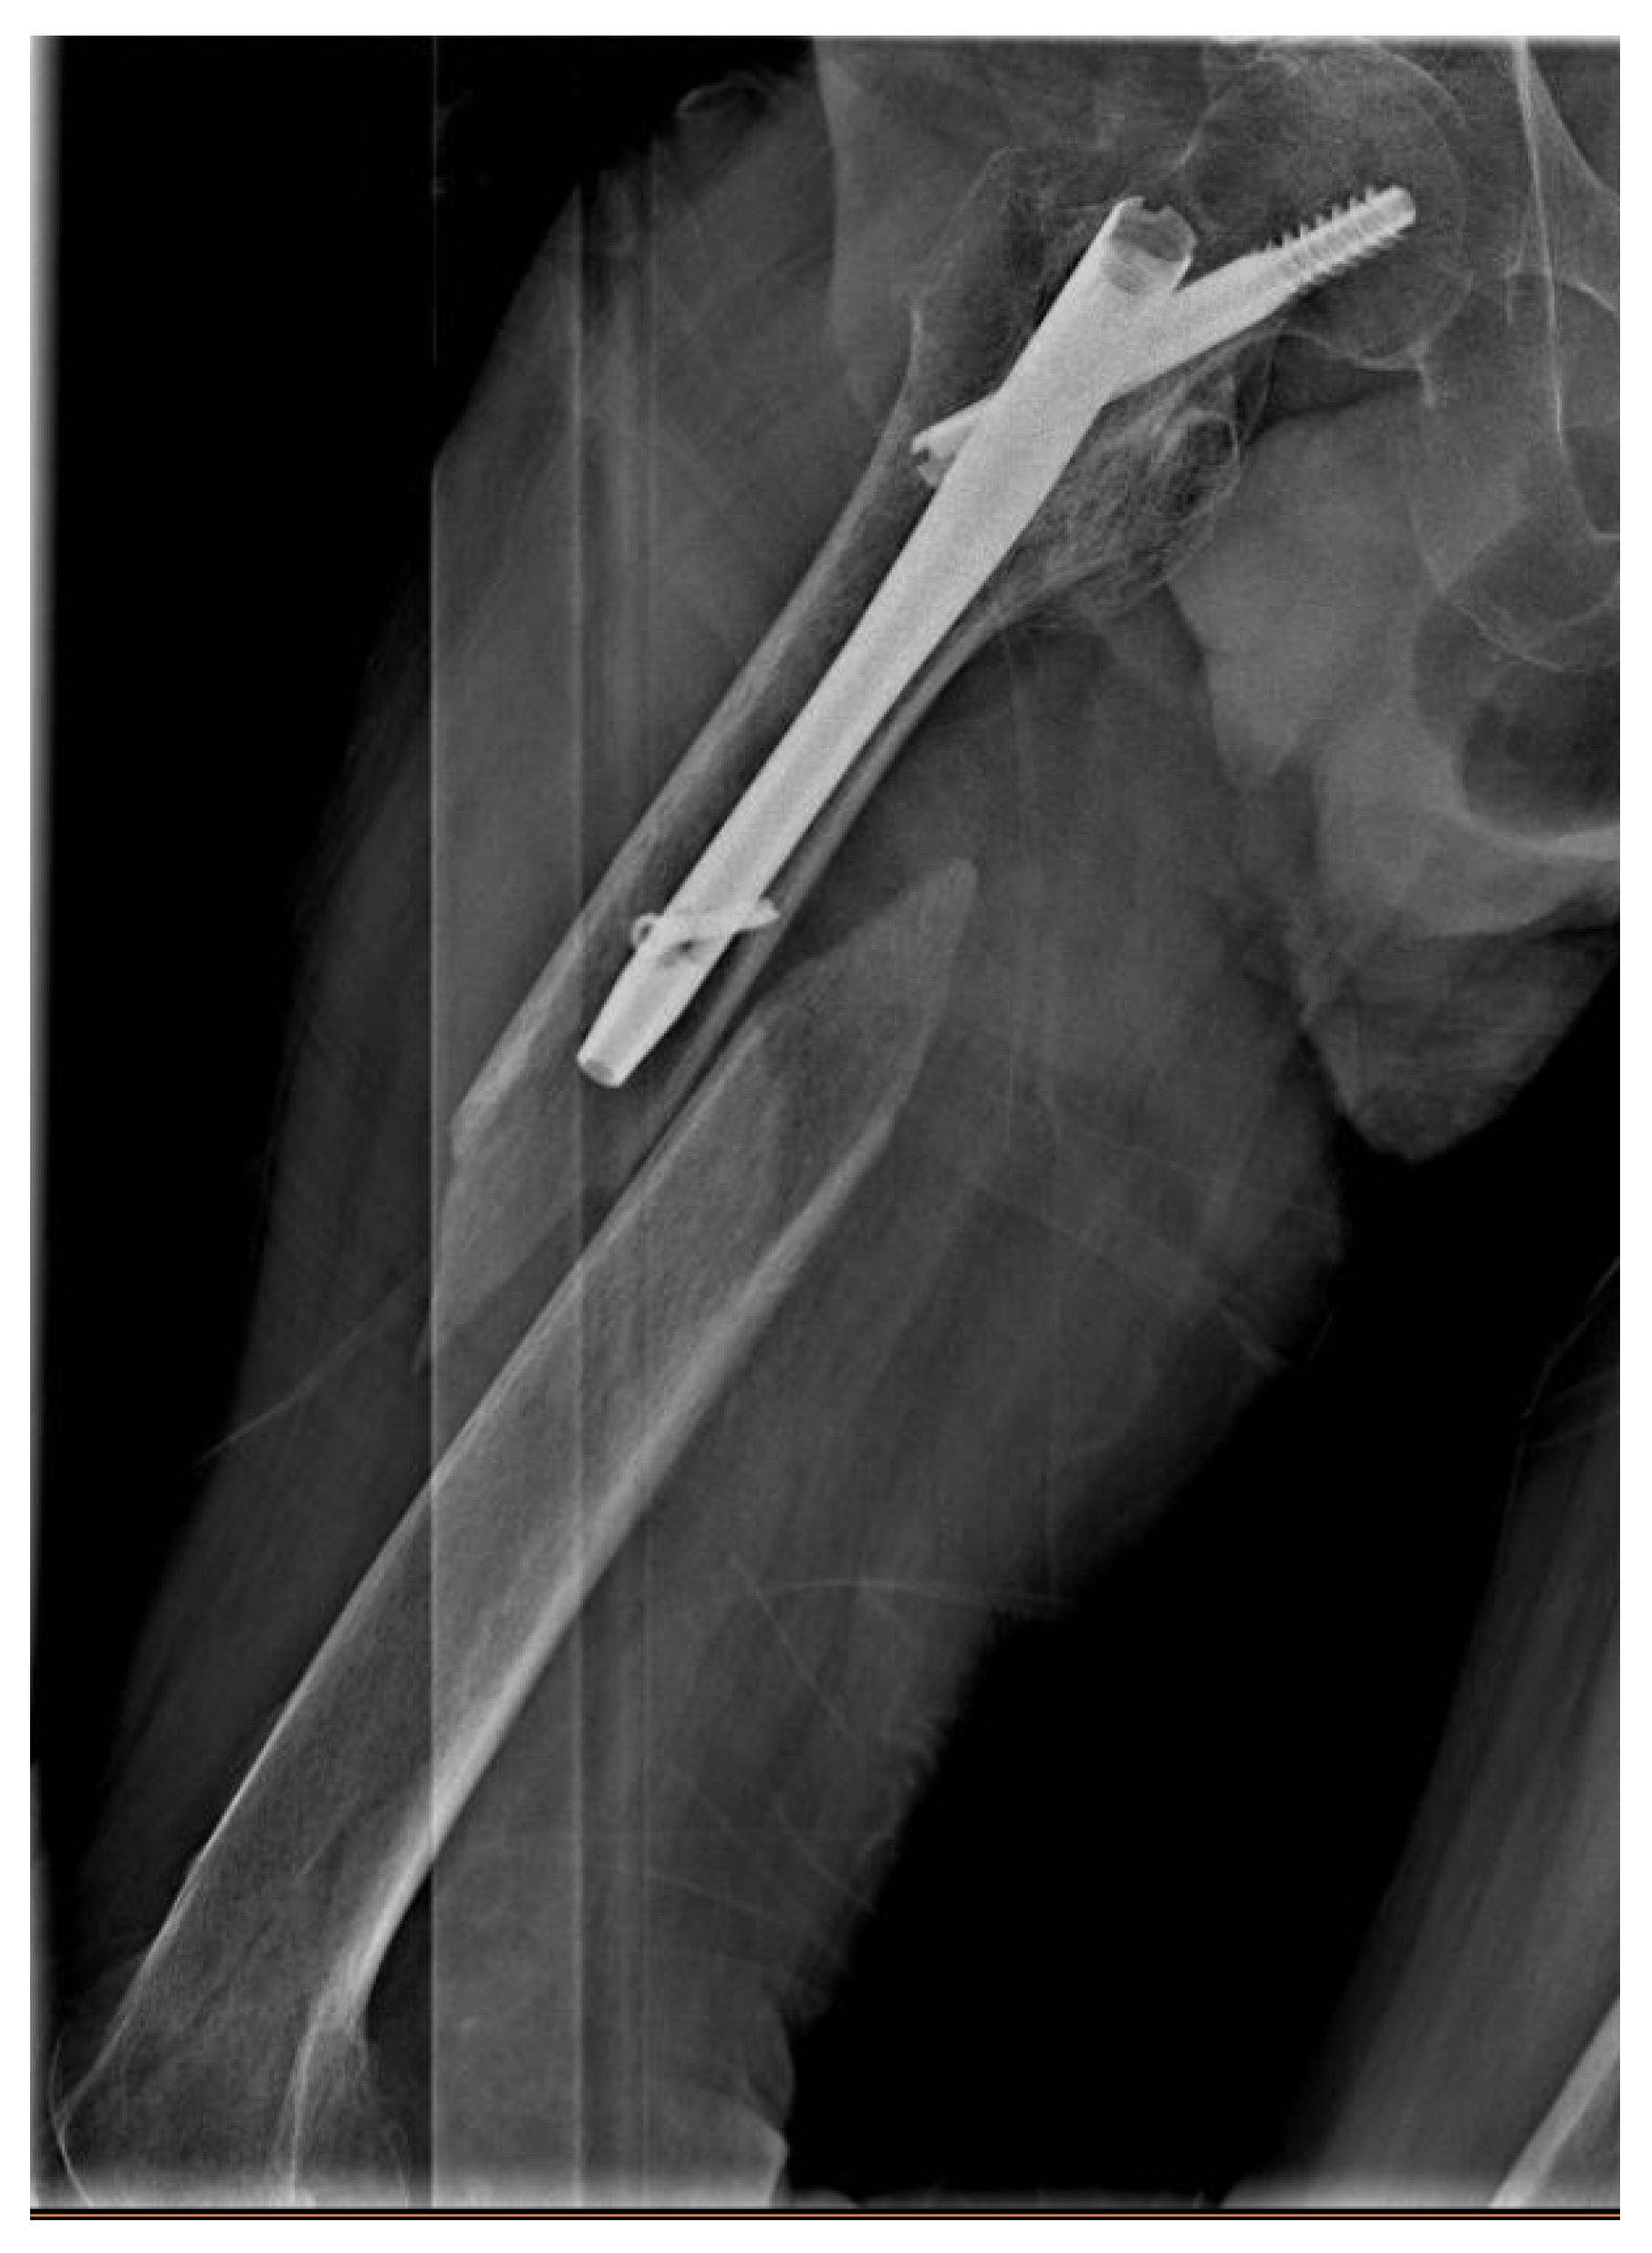

- γ: nail;

| Nail | Gamma (γ) |